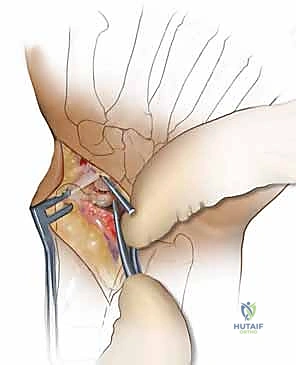

1. النهج الجراحي الأمامي (Volar Approach)

يُفضل البروفيسور هطيف في معظم حالات عدم الالتئام المصحوبة بتشوه محدب استخدام المدخل الأمامي (من جهة راحة اليد).

لماذا؟ لأن هذا النهج يحافظ على الإمداد الدموي الظهري المتبقي (والذي ذكرنا أنه يمثل 70% من تغذية العظم)، كما أنه يوفر رؤية ممتازة للكسر، ويسهل عملية تصحيح التشوه المحدب بفتح زاوية العظم من الأمام.

2. تنظيف موقع عدم الالتئام (Debridement)

بمجرد الوصول إلى العظم الزورقي، يقوم الجراح بإزالة النسيج الليفي المتكون بين شظايا العظم. ثم يتم استخدام أدوات دقيقة (Curettes or high-speed burrs) لكشط وحفر حواف العظم المتصلبة والميتة حتى يتم الوصول إلى عظم إسفنجي صحي ينزف دماً. هذه العلامة تُعرف طبياً بـ "علامة البابريكا" (Paprika Sign)، وهي مؤشر حاسم على أن العظم المتبقي حي وقادر على الالتئام.

4. وضع الرقعة الوتدية وتصحيح التشوه (Placing the Volar Wedge)

هذه هي الخطوة الأكثر أهمية في استعادة وظيفة الرسغ. يتم إدخال الرقعة العظمية الوتدية في الفجوة بين جزئي العظم الزورقي من الناحية الأمامية. هذا الإجراء يحقق هدفين في وقت واحد:

* علاج بيولوجي: الرقعة توفر خلايا عظمية حية وهيكلاً لنمو عظم جديد.

* علاج ميكانيكي: الشكل الوتدي للرقعة يدفع جزئي العظم المتقاربين للابتعاد من الأمام، مما يصحح "التشوه المحدب" (Humpback Deformity) ويعيد العظم الزورقي إلى طوله وشكله التشريحي الطبيعي، وبالتالي يعيد التوازن الميكانيكي لكامل مفصل الرسغ.